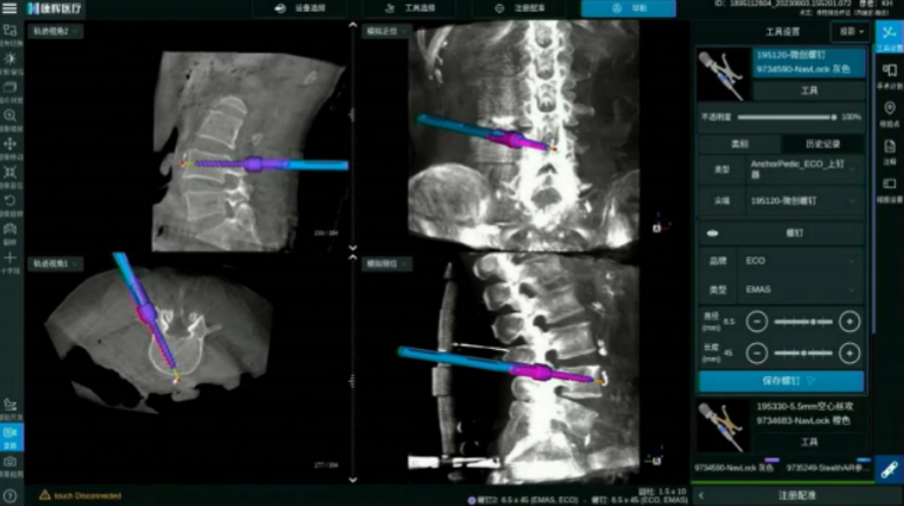

颈椎后路内固定

全程可视化带来颈椎手术精准性的提升

ECO/Anchor与导航化学连接 螺纹级可视

电动手柄配合导航实现可视化动力置钉

· 无导丝置钉流程, 手术更加精准安全

· 开路、丝攻、置钉,手术全程步步实时可视

· 实时呈现手术工具、 内植入物清晰边界